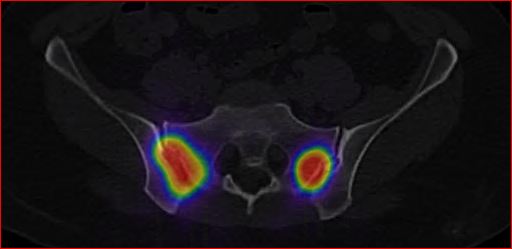

Následně byla provedena verifikační scintigrafie (obr.3) k posouzení distribuce RF (s využitím spektra brzdného záření).

/ Obr.3.: SPECT/CT Distribuční scintigrafie – distribuce RF v obou SI skloubeních.

/